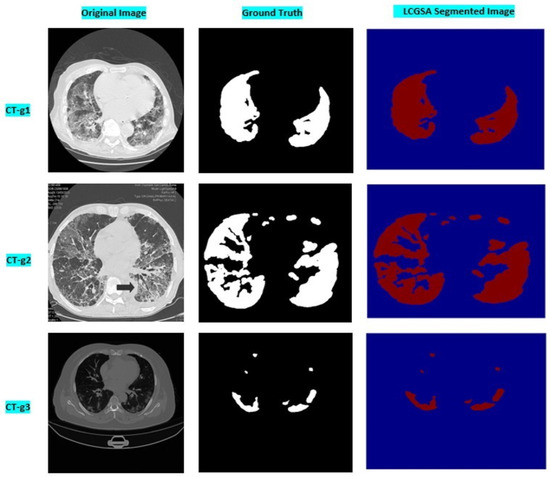

Levy Flight and Chaos Theory-Based Gravitational Search Algorithm for Image Segmentation

by Sajad Ahmad Rather and Sujit Das

Mathematics 2023, 11(18), 3913; https://doi.org/10.3390/math11183913 - 14 Sep 2023

Cited by 7 | Viewed by 2257

Abstract

Image segmentation is one of the pivotal steps in image processing due to its enormous application potential in medical image analysis, data mining, and pattern recognition. In fact, image segmentation is the process of splitting an image into multiple parts in order to [...] Read more.

Image segmentation is one of the pivotal steps in image processing due to its enormous application potential in medical image analysis, data mining, and pattern recognition. In fact, image segmentation is the process of splitting an image into multiple parts in order to provide detailed information on different aspects of the image. Traditional image segmentation techniques suffer from local minima and premature convergence issues when exploring complex search spaces. Additionally, these techniques also take considerable runtime to find the optimal pixels as the threshold levels are increased. Therefore, in order to overcome the computational overhead and convergence problems of the multilevel thresholding process, a robust optimizer, namely the Levy flight and Chaos theory-based Gravitational Search Algorithm (LCGSA), is employed to perform the segmentation of the COVID-19 chest CT scan images. In LCGSA, exploration is carried out by Levy flight, while chaotic maps guarantee the exploitation of the search space. Meanwhile, Kapur’s entropy method is utilized for segmenting the image into various regions based on the pixel intensity values. To investigate the segmentation performance of ten chaotic versions of LCGSA, firstly, several benchmark images from the USC-SIPI database are considered for the numerical analysis. Secondly, the applicability of LCGSA for solving real-world image processing problems is examined by using various COVID-19 chest CT scan imaging datasets from the Kaggle database. Further, an ablation study is carried out on different chest CT scan images by considering ground truth images. Moreover, various qualitative and quantitative metrics are used for the performance evaluation. The overall analysis of the experimental results indicated the efficient performance of LCGSA over other peer algorithms in terms of taking less computational time and providing optimal values for image quality metrics. Full article

(This article belongs to the Section E1: Mathematics and Computer Science)

Show Figures

Graphical abstract